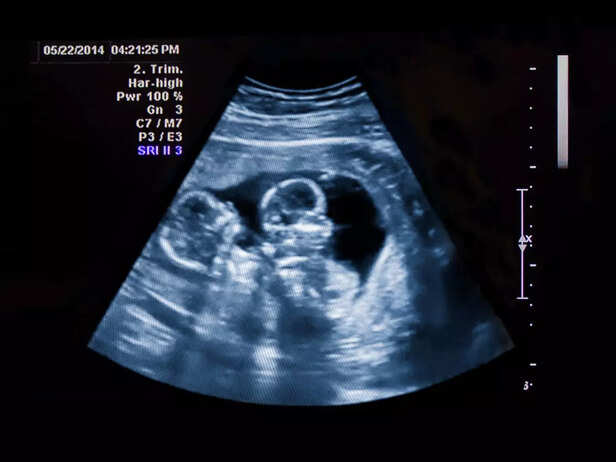

Twin pregnancy

TTTS is primarily linked to placental abnormalities. In monochorionic pregnancies (shared placenta), the twins are at higher risk for CTS due to the intricate vascular connections in the placenta.

b. Ultrasound Evaluation

twin ultrasound

Early diagnosis is essential. Regular ultrasounds can help detect TTTS by measuring amniotic fluid levels and assessing blood flow within the placenta.